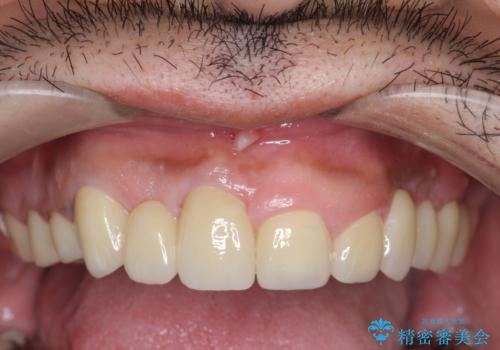

オールセラミッククラウン ブリッジによる欠損歯の補綴

- 歯がない左側でものが咬めず、右側で咬むと歯が痛むので診て欲しいといらっしゃった方の症例です。

根尖病変が認められる歯は再根管治療を行い、歯根が破折していた左上4は抜歯しました。

インプラントは希望されなかったため、左側は1番から7番のロングスパンブリッジによる補綴を行いました。

今回用いたオールセラミッククラウンは、ジルコニアフレームという白い素材の上にセラミックを盛っているため審美性が非常に高いのが特徴です。

またジルコニアは人工ダイヤモンドの材料にも使われているほど高い強度を持っており、そのためオールセラミッククラウンは審美性だけでなく、奥歯やブリッジの補綴も可能とするクラウンです。